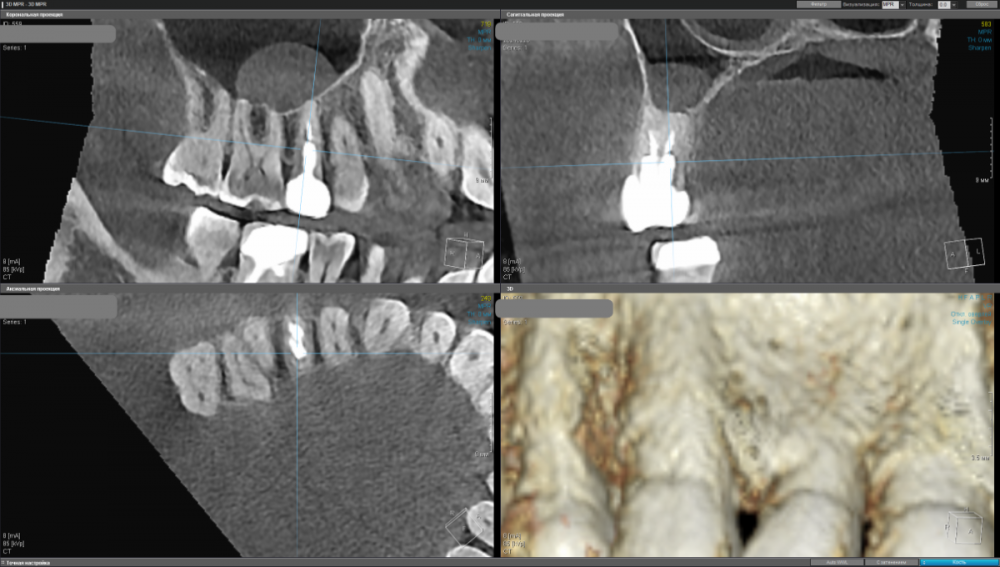

kamacho Опубликовано 24 февраля, 2024 Автор Поделиться Опубликовано 24 февраля, 2024 Попробую привлечь ваше внимание дополнительными снимками. Вопросы которые я себе задаю когда смотрю на КТ: 1) Между 14 и 15 зубом, это убыль фуркации или артефакт при съемке кт ? 2) В районе 37 ого зуба это артефакт или кариес ? Я пытаюсь санировать ротовую полость уже наверное лет пять, и никогда не удается решить проблему. Прошел множество клинник (наверное штук 5-6, включая 1 зарубежную). Но после попыток лечения, возникает одна и таже проблема, как только начинаю добавлять углеводы(не сладости) в рацион, какой-то очаг инфекции дает о себе знать. Буду очень признателен если поможете советом или догадкой. Ссылка на комментарий

kamacho Опубликовано 24 февраля, 2024 Автор Поделиться Опубликовано 24 февраля, 2024 (изменено) Так же приложу документ-опись риентгенолога по всем зубками с изображениями. снимок был сделан в 22 году. Наврятли кто-либо захочет перечитывать такое количество информации ради развлечения. Но для истории добавлю. Изменено 24 февраля, 2024 пользователем kamacho Ссылка на комментарий

Carioznik Опубликовано 25 февраля, 2024 Поделиться Опубликовано 25 февраля, 2024 15.02.2024 в 18:43, kamacho сказал: есть ли показания для лечения этого зубика? По идее есть, но нужно разбираться 15.02.2024 в 18:43, kamacho сказал: Могут ли не до конца пролеченные корни вызывать такую симптоматику ? Нет 17 часов назад, kamacho сказал: Между 14 и 15 зубом, это убыль фуркации Нет. Похоже, что на 14 есть кариес. Возможно это и причина кровоточивости и запаха. Но нужно смотреть настоящую КТ , а не скрины. 18 часов назад, kamacho сказал: районе 37 ого зуба это артефакт или кариес ? Больше на артефакт похоже, но это не точно: нужно смотреть настоящую КТ , а не скрины 1 Ссылка на комментарий